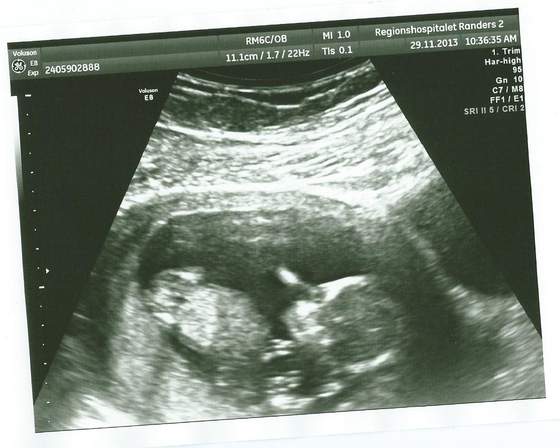

Tutaj Dzidzia jeszcze do góry nogami... później zrobiła fikołka

Zobacz załącznik 596491

Zobacz załącznik 596492